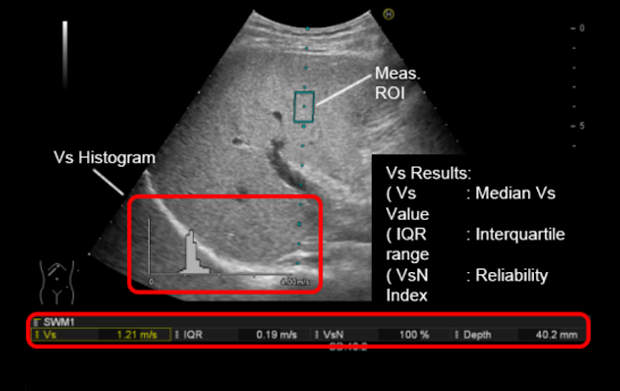

Shear Wave Measurement (SWM) gwarancją wiarygodności pomiaru

Zgodnie z wytycznymi Światowej Federacji Ultrasonografii w Medycynie i Biologii (WFUMB) SWM można sklasyfikować jako punktowy pomiar prędkości fali ścinającej/poprzecznej.  Mierzy on prędkość propagacji fali ścinającej/poprzecznej (Vs). SWM posiada funkcję wyświetlania wskaźnika niezawodności (VsN) dla pomiaru prędkości propagacji fali ścinającej/poprzecznej (Vs) i automatycznie wykonuje wiele pomiarów Vs w obszarze zainteresowania (ROI). Wszystko to za pomocą jednego przycisku. Procent prawidłowo wykrytych pomiarów jest wyświetlany ilościowo jako wskaźnik poprawności wykonania badania (VsN).

•    powtarzalność wartości Vs dzięki wielokrotnym pomiarom po naciśnięciu jednego przycisku;

•    dokładniejsze wyniki pomiarów dzięki wskaźnikowi poprawności wykonania pomiaru wyświetlanemu jako wskaźnik niezawodności (VsN);

•    zmniejszenie całkowitej liczby koniecznych pomiarów;

•    automatyczne przechwytywanie obrazu B-mode, automatyczne przechowywanie i uśrednianie wielu wartości pomiarowych wspiera wydajny przepływ pracy.